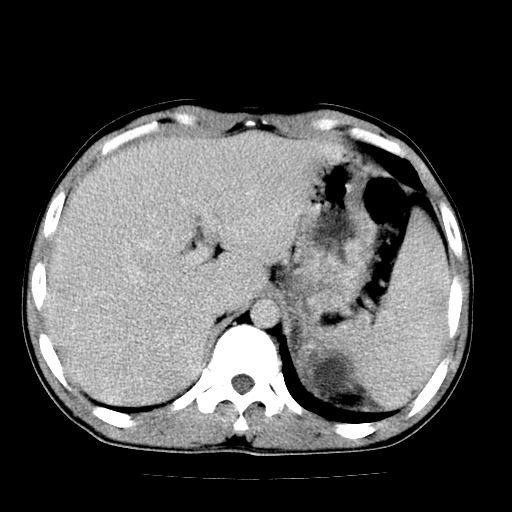

以下是引用天南地北在2007-4-30 13:36:00的发言:[br]支持慢性胰腺炎伴有假性囊肿

以下是引用andymaomao在2007-4-30 14:28:00的发言:[br]支持:1.慢性胰腺炎并假性囊肿形成可能;[br] 2.左肾形态稍增大,旋转不良。